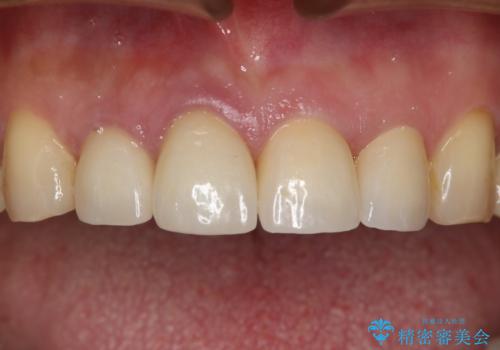

セラミックインレー修復 虫歯をとって白い歯へ

- 初診時、色が黒ずんでいる歯があり気になるとのことでいらっしゃいました。

診査の結果、下顎左右の前から6番目の歯に深い虫歯があったため治療をすることになりました。

歯の外形全体を削る必要性はなかったため詰め物(インレー)タイプで修復していく運びとなりました。(e-max プレスインレー)

虫歯=歯が痛い というイメージがある方も多いかもしれませんが、実際には時間をかけて少しずつ進行する虫歯は、無症状に歯の奥深くまで進行していることが多くあります。今回も歯の見た目の悪さを気にして来院されましたが、実際には神経の近くまで虫歯が広がっており、神経の治療が必要になる一歩手前の状態でした。早めの治療を行えたことで詰め物での治療で治すことができました。